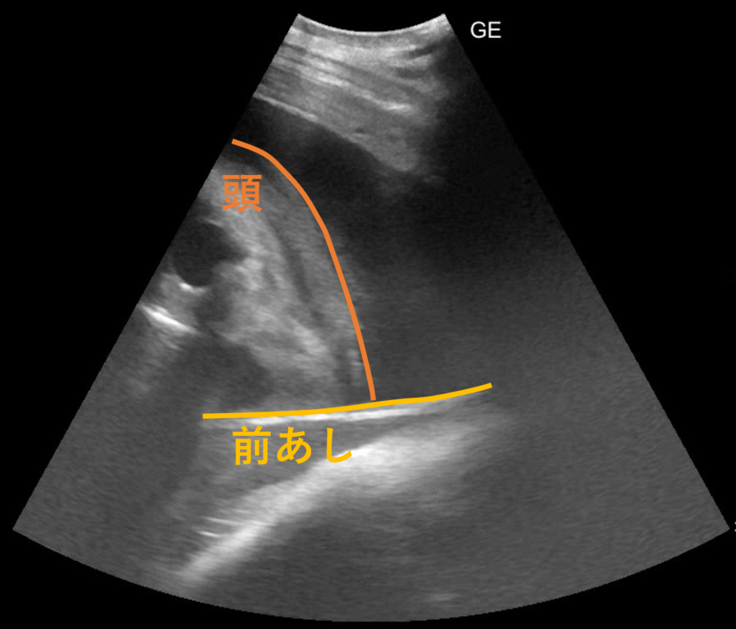

今回の検査で見ることができた画像を紹介します。

これだと何が映っているのかよくわからないので、線を引いてみました。

最初の画像と見比べていただくと、何となく見えてくるでしょうか。メイのお腹の中の子ゾウの前肢と頭です。目に見える黒い部分が、目なのか、鼻の奥を捉えることができたのかははっきりせず、今後の検査で姿勢があえば追っていく予定です。

クラウドファンディングページで紹介した2024年9月の画像では、胸からお腹にかけてを1つの視野で観察できていました。約半年がたち、検査機器で見ることができる25㎝程度の深さでは、たまたま近くに来ている頭の一部や前あしの一部が観察できる、というところまで成長しています。